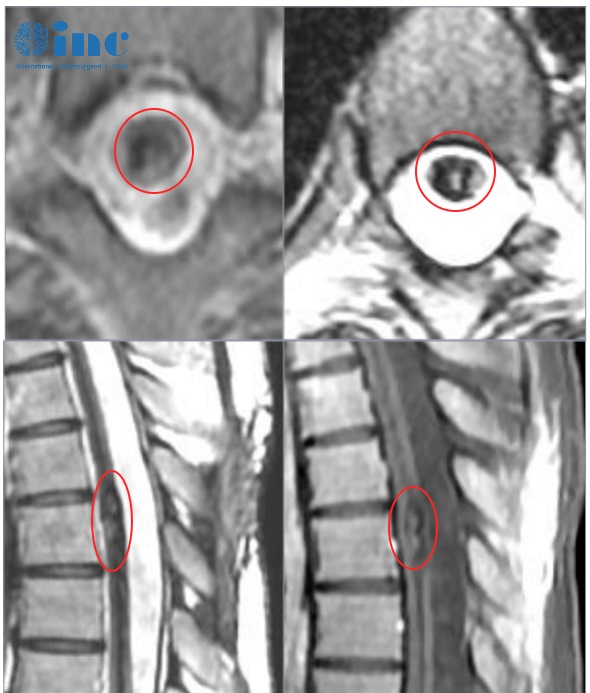

影像

北京時間2025年10月22日,巴教授于蘇州大學附屬第四醫(yī)院完成這臺海綿竇區(qū)占位病變示范手術。

手術難在何處?在于其位置深、解剖關系錯綜復雜。該區(qū)域不僅包繞頸內動脈,更密集走行著動眼神經、滑車神經、三叉神經和外展神經等重要顱神經。術中稍有不慎,極可能導致功能障礙。因此,手術的核心目標是在全力保護血管與神經功能的基礎上,最大限度地切除病變。

最終,在巴教授與國內神經外科團隊的緊密協作下,這個血供豐富的腫瘤得到了滿意的切除。